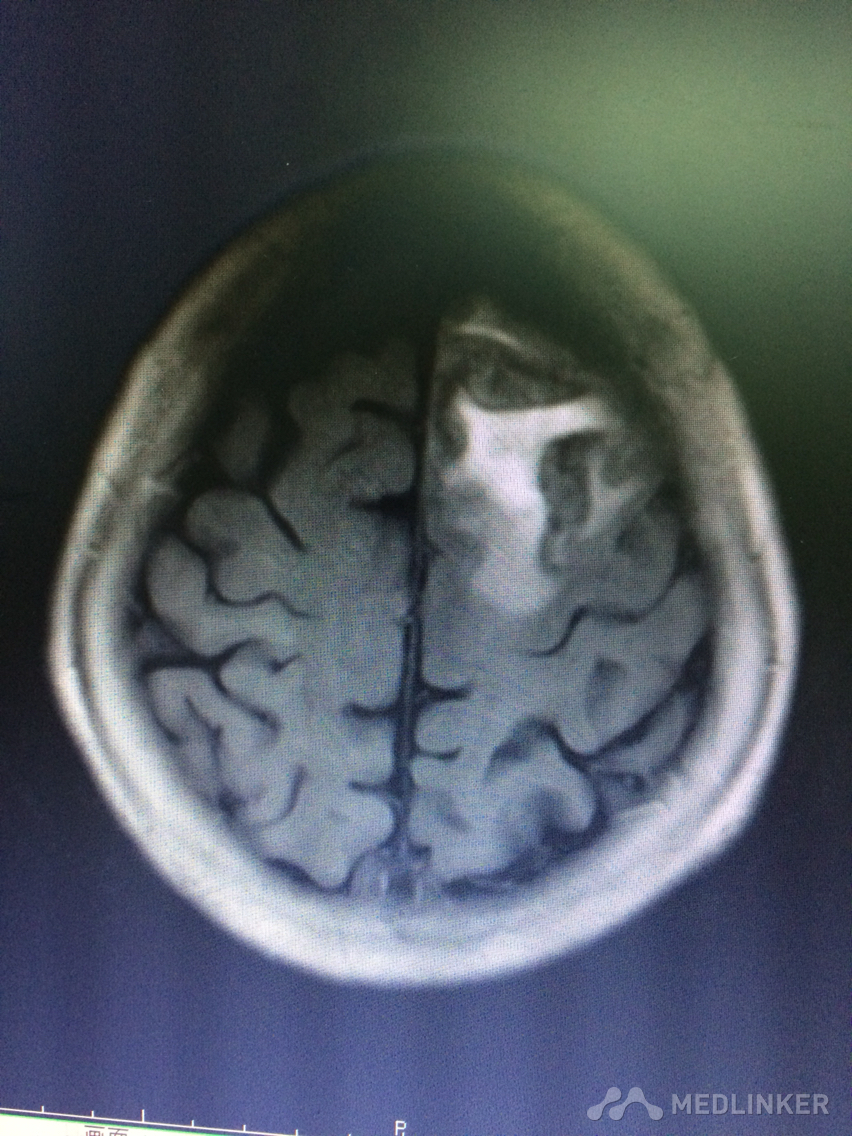

看看这MRI,奇怪啊,快来帮忙看看?

患者78岁老年女性,以精神行为异常和认知障碍为主要表现